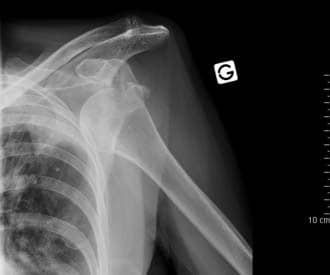

Clinically, dislocations at the shoulder are described by where the humeral head lies in relation to the glenoid fossa. Anterior dislocations are the most prevalent (95%), although posterior (4%) and inferior (1%) dislocations can sometimes occur. Superior displacement of the humeral head is generally prevented by the coraco-acromial arch.

An anterior dislocation is usually caused by excessive extension and lateral rotation of the humerus. The humeral head is forced anteriorly and inferiorly – into the weakest part of the joint capsule. Tearing of the joint capsule is associated with an increased risk of future dislocations. Hill-Sachs lesions (impaction fracture of posterolateral humeral head against anteroinferior glenoid) and Bankart lesions (detachment of antero-inferior labrum with or without an avulsion fracture) can also occur following anterior dislocation.

Indeed, so-called ‘reverse Hill-Sachs lesions’ (impaction fracture of anteromedial humeral head) and ‘reverse Bankart lesions’ (detachment of posteroinferior labrum) can be seen in posterior dislocations.

The axillary nerve runs in close proximity to the shoulder joint and around the surgical neck of the humerus, and so it can be damaged in the dislocation or with attempted reduction. Injury to the axillary nerve causes paralysis of the deltoid, and loss of sensation over regimental badge area

Fig 1.4 - Anterior dislocation of the shoulder joint.

Fig 5

Anterior dislocation of the shoulder joint.